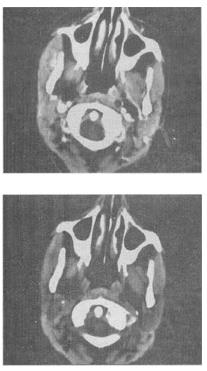

- 单项选择题 女,16岁,右侧面颊部肿胀,CT扫描如图所示,最可能的诊断是()。

A、右侧咬肌区血管瘤

B、右侧咬肌区脂肪瘤

C、右侧咬肌区皮样囊肿

D、右侧咬肌区淋巴管瘤

E、右侧咬肌区慢性淋巴管炎

- A